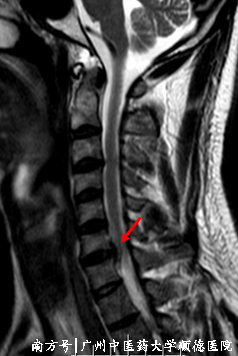

37岁的黄先生在四年前的某天,一觉醒来发现自己脖子痛,左上肢疼痛麻痹,活动不自在。随后去医院就诊,黄先生接受药物和理疗治疗后,症状得以缓解,但仍感觉左上肢活动不是很灵活,麻痹不舒服,遂做了颈椎MRI检查。医生告诉黄先生,颈椎MRI提示C6/7椎间盘突出了,压迫着左侧C7神经根,导致了黄先生的颈痛,左上肢麻痹疼痛。考虑症状出现时间不是很久,建议牵引、理疗配合消炎止痛、营养神经等处理。

↑ C6/7椎间盘突出,左侧神经受压。